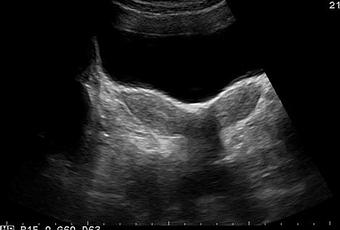

Un útero bicorne es una anormalidad en la fusión de los conductos de Müller, donde hay fusión incompleta del segmento del conducto de Müller que se desarrolla en el útero, lo que resulta en un útero con dos cuernos. El diagnóstico de útero bicorne es importante ya que se asocia con infertilidad, pérdidas recurrentes de embarazos y malpresentación.

Las anomalías uterinas congénitas ocurren en 0.1 a 3% de las mujeres y se deben a un desarrollo anormal de los conductos paramesonéfricos. El fracaso de la fusión de estos conductos ocasiona la división del útero en dos cuernos (útero bicorne) si falla parcialmente la fusión y la duplicación completa del útero, el cuello uterino y la vagina (didelfo) si hay una falla total de la fusión. Se asocia con complicaciones del embarazo, como aborto espontáneo, malpresentación y parto prematuro. La infertilidad no suele ser un problema con este tipo de malformación porque la implantación del embrión no se ve afectada. Las anomalías asociadas del tracto renal son comunes. Los métodos preferidos para obtener imágenes de las anomalías uterinas son la ecografía, la histerosalpingografía o la resonancia magnética.